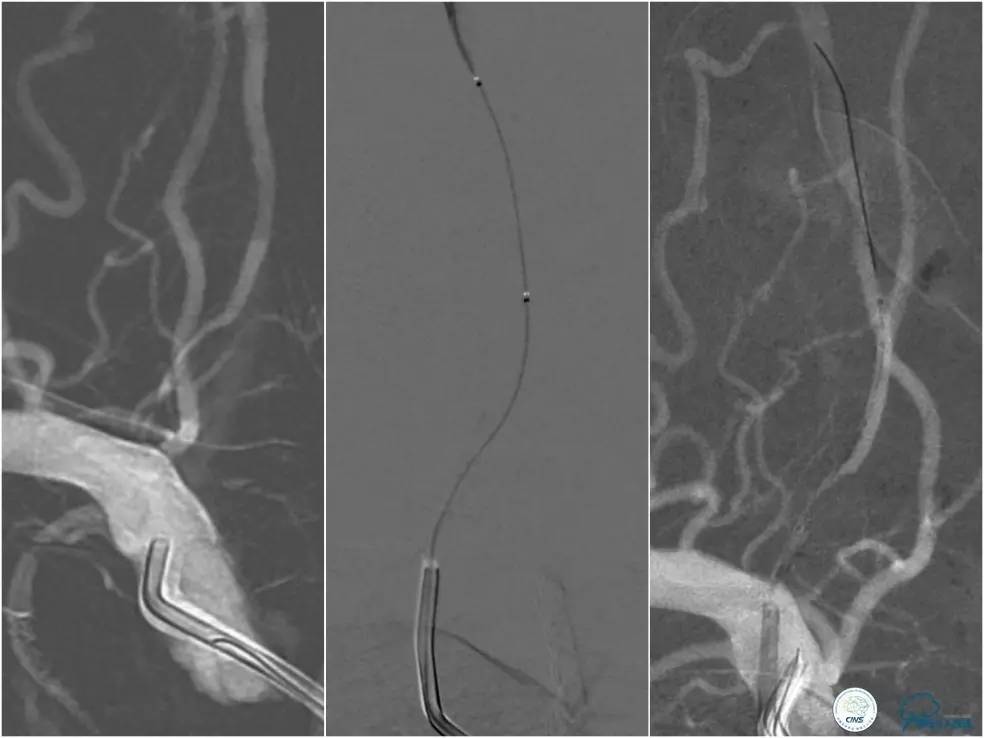

全麻下右侧股动脉穿刺置入8F动脉鞘,6F导引导管到位,送入Traxcess(0.014″200cm)微导丝+Echelon-10微导管小心通过右侧椎动脉V1段狭窄处至V2段远端,交换撤出Traxcess微导丝,送入Transend(0.014″300cm)微导丝至V2段远端(图10)。

图10

Ultra-Soft球囊(3.0mm×20mm)于狭窄处预扩张后置入EXCEL支架(4.0 mm× 24mm),球扩后造影见支架贴壁良好,远端血管显影好,前向血流TICI3级。6F导引导管沿微导丝通过右椎动脉V1段支架至V2段(图11)。

图11